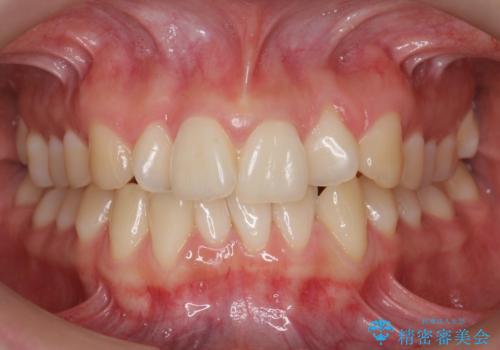

前歯がねじれている 奥歯を後ろに下げて歯を抜かずに並べました

- 前歯のねじれを主訴に来院。

前から2番目の歯がねじれて下の歯の内側に入っていました。

また、奥歯のかみ合わせが上の奥歯が若干前に並んでおり、それで前歯が入りきらずにねじれていました。

歯を抜かずに奥歯を後ろに下げてマウスピースで矯正しています。

上の奥歯を後ろに下げて前歯のねじれを治すスペースを確保しました。